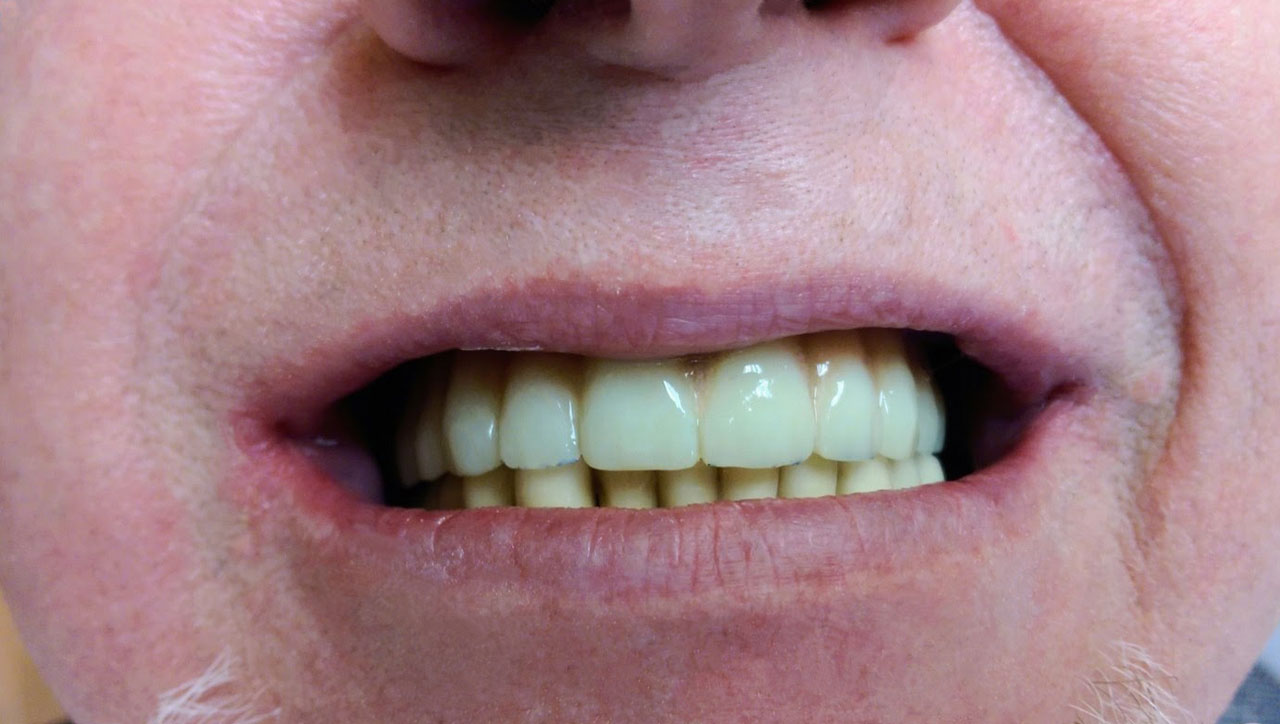

• esettanulmany-12

72 órával az alsó-felső állcsont teljes implantációs helyreállítása után, így mosolyog a páciens a beragasztott, fix hidakkal.